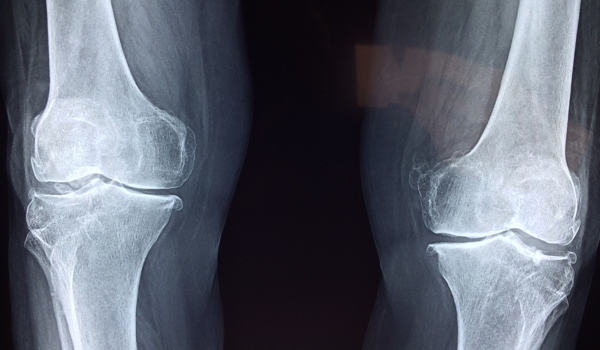

- Imaging studies:

- X-rays and CT scans: Identify bone lesions or fractures

- MRI: Detects marrow infiltration and nerve compression

- PET scan: Used for staging and detecting cancer spread